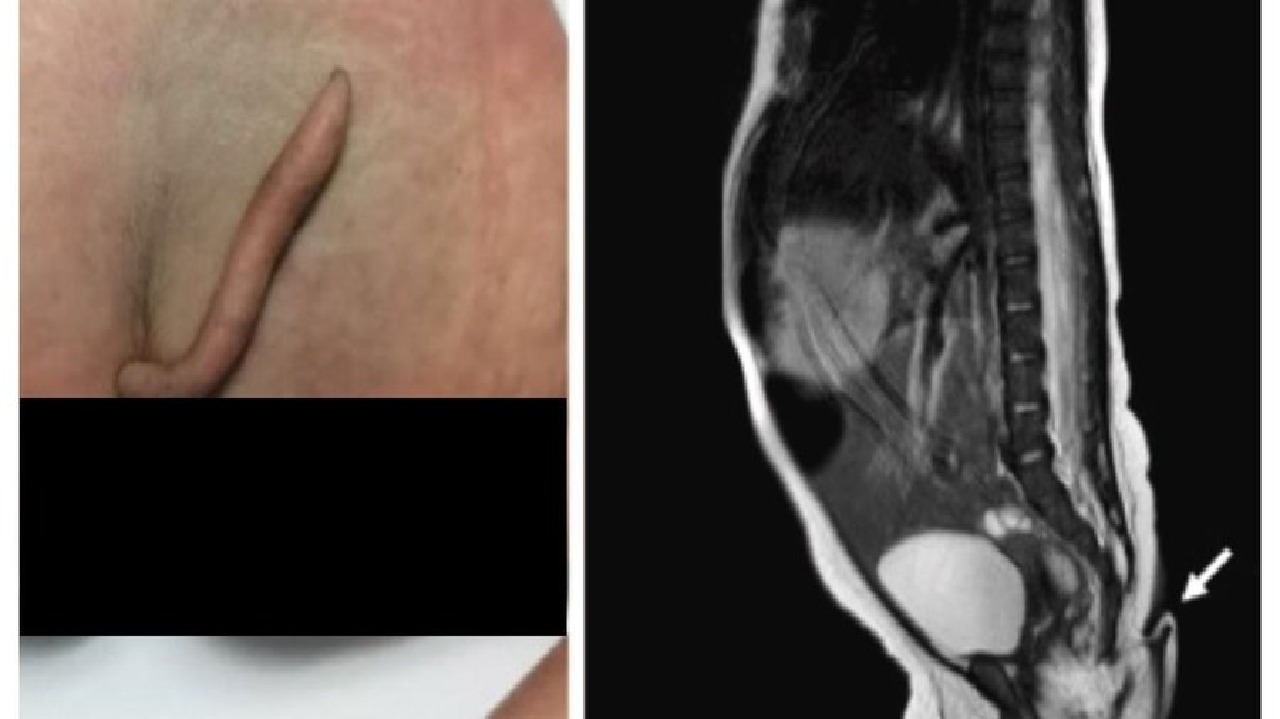

بالصور.. حالة نادرة لنمو ذيل أسفل ظهر مراهق منذ ولادته